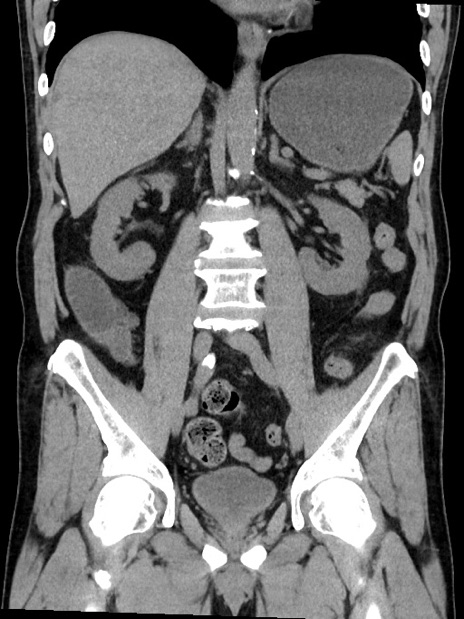

症例35(冠状断像)

【症例】70歳代 男性

【主訴】腹部膨満、嘔吐

【現病歴】昨日より腹部膨満感出現。本日増悪し、仙痛出現。嘔吐あり、受診。

【既往歴】糖尿病、胆摘後

【身体所見】BP 149/80mmHg、HR 74/min、BT 35.9℃、腹部:膨満、軟、圧痛なし。腸雑音減弱あり。上腹部正中切開瘢痕あり。

【データ】WBC 13500、CRP 1.72